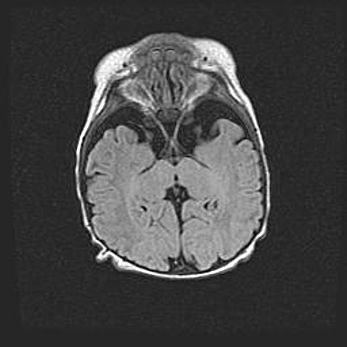

Неполная лизэнцефалия (пахигирия). Открытая гидроцефалия.

Возраст: 17 дней

Вес: 3110 г

Пол: мужской

Окружность головы: 33,5 см

Срок гестации: 35-36 недель

Лизэнцефалия—недоразвитие корковой пластинки и мозговых извилин в результате нарушения миграции нейронов коры. Поверхность мозговых полушарий гладкая. Микроскопически выявляется отсутствие нормальных слоев коры и скопление групп нейронов в подкорковом белом веществе.

Пахигирия—уменьшение числа вторичных извилин. В пораженном полушарии нервные клетки образуют толстый недифференцированный слой с неправильно расположенными нервными волокнами и группами гетеротопных клеток. Нервные клетки незрелые. Белое вещество истончено. При этом нередко аномально развит корково-спинномозговой путь.